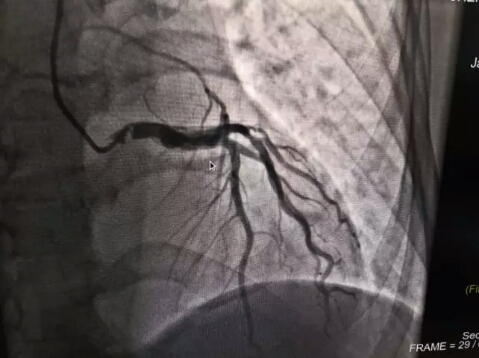

除開展全身(shēn)各部位常規檢查外,還先後開展了(le)全身(shēn)血管CTA成像、骨關(guān)節CT三維重建、磁共振擴散加權成像DWI、灌注成像PWI、磁敏感成像SWI、胰膽管水成像MRCP、泌尿系水成像MRU、内聽(tīng)道水成像、外周血管介入診療、消化(huà)道支架成形術、椎體(tǐ)成形術、椎間(jiān)盤消融術、經皮穿刺活檢術等新(xīn)技術。

全身(shēn)多部位血管造影及介入治療